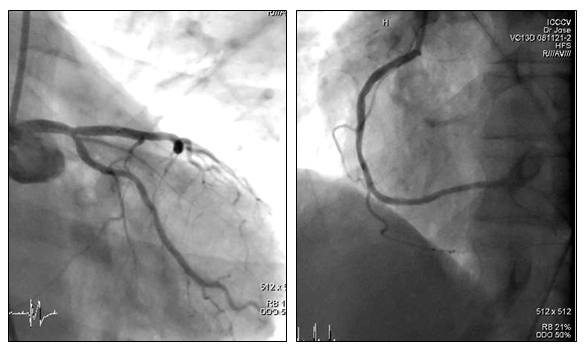

La coronariografía realizada el 12/10/2011 demostró arterias epicárdicas sin lesiones angiográficamente significativas (fig. 1). El paciente continuó con tratamiento anti-isquémico sin alivio del dolor precordial, por lo que se decide realizar un estudio de perfusión miocárdica con el objetivo de documentar la existencia de isquemia miocárdica que justificara los síntomas.